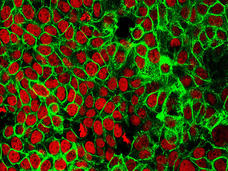

Concentración en una adicción en cáncer de seno triple negativo

Un nuevo método para interrumpir los genes que promueven la formación y diseminación de tumores puede prometer que se pueda tratar un tipo de cáncer de seno que es agresivo y difícil de tratar.